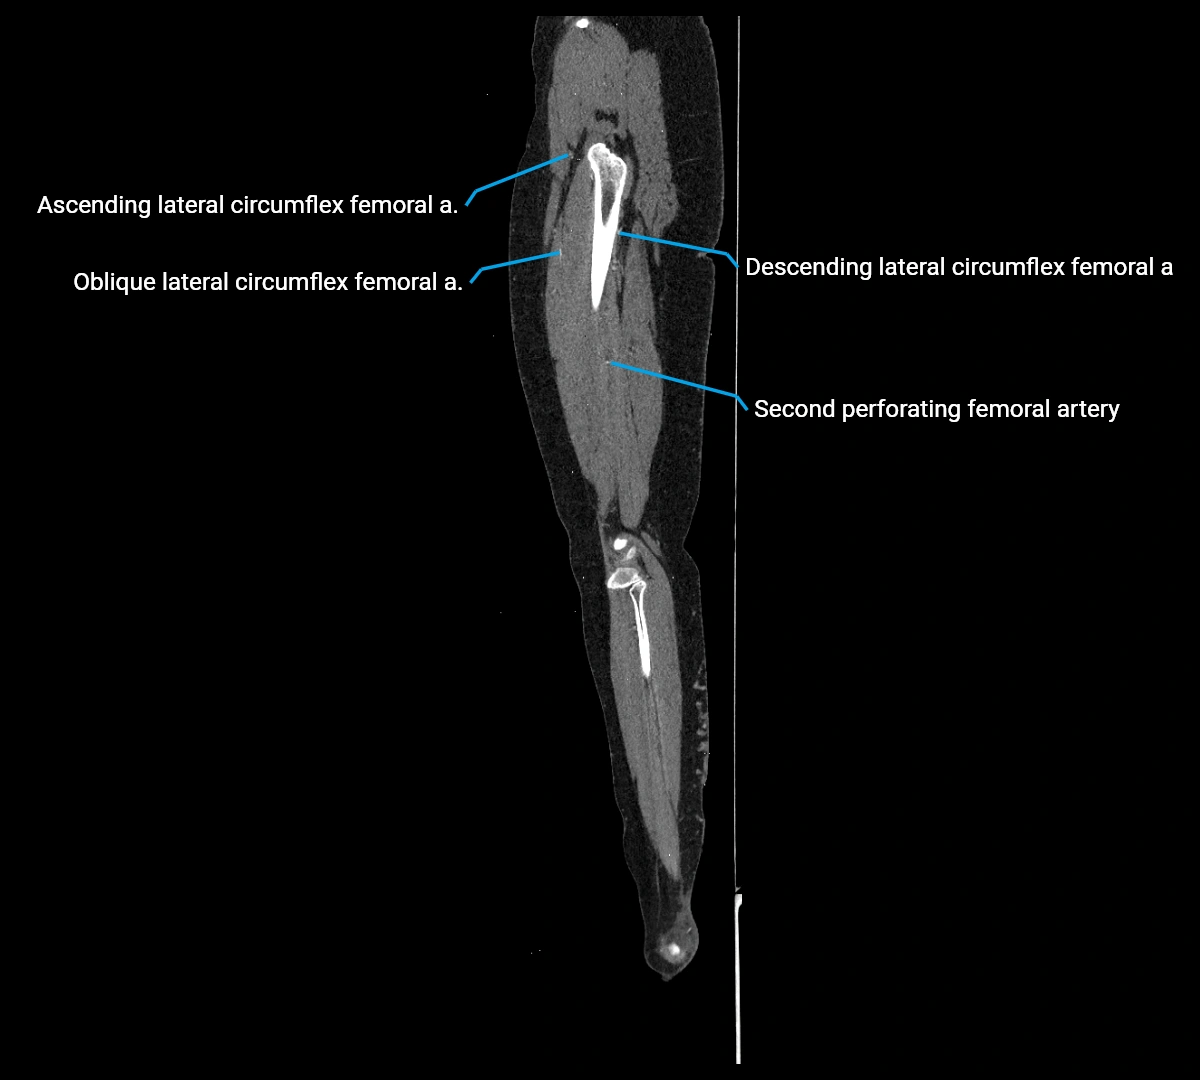

CT images

image